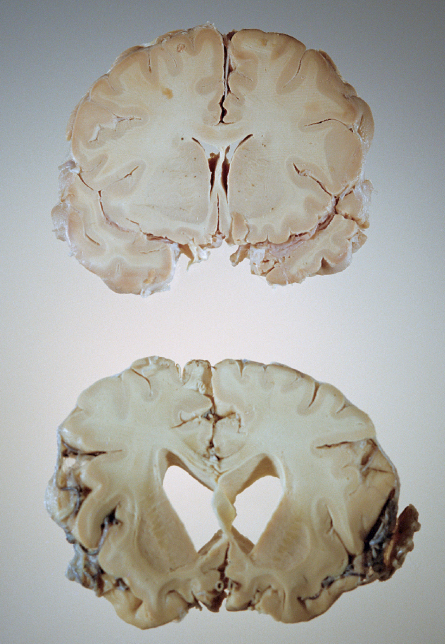

The polite term for what Alzheimer’s disease does to the brain is “neurodegeneration.”

In reality, it’s more like violent, indiscriminate devastation. Alzheimer’s scrambles communication channels, incites massive inflammation and demolishes entire brain regions as once plump cells shrivel and die, burying memories in the wreckage. As the attack intensifies, Alzheimer’s gradually strips away a person’s mind, and ultimately the cognitive abilities that permit a conversation with a loved one, a smile or a taste of food.

Alzheimer’s is unlike anything else clinicians have treated: In most cases, no one knows what causes it. It can’t be definitively diagnosed until a pathologist cuts into the dead brain. There is no known cure or therapy for prevention, and even if there were, it wouldn’t be clear when to use either one. Many believe the disease causes its irreparable damage years before symptoms appear.